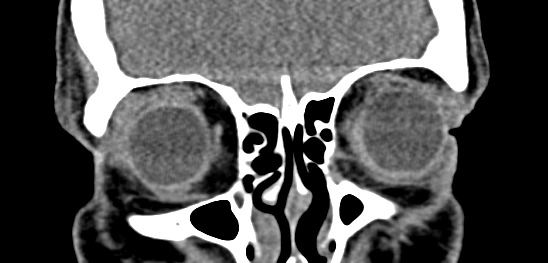

Орбиты (или глазницы) – это костные углубления в лицевом черепе, где расположены глазные яблоки, окруженные жировой клетчаткой, а также слезные железы, слезные каналы, сосуды, нервы, мышцы и связки глаза. Такая небольшая по объему область содержит важные анатомические структуры, обеспечивающие нормальную функцию органа зрения.

Кроме того, область орбиты тесно связана с близлежащими структурами – полостью черепа с расположенным в ней головным мозгом, а также с полостью носа, околоносовыми пазухами и носоглоткой. Различные патологические процессы могут развиваться как в самой глазнице, так и в околоорбитальных структурах, но при этом распространяться на область орбит.

Мультиспиральная компьютерная томография лучше всего визуализирует ткани с высокой плотностью, к которым, в частности, относится костная ткань. Это делает КТ незаменимой при диагностике травматических повреждений глазниц, а также для выявления инородных тел орбит.

По результатам КТ орбиты глаза врач может оценить состояние:

- костных стенок глазницы, верхней и нижней глазничных щелей;

- глазных яблок

- мышц глаза: нижней, верхней, косой, прямых мышц (латеральной и медиальной);

- зрительных нервов;

- слезных желез;

- ретробульбарной (расположенной позади глазного яблока) клетчатки.

КТ орбит позволяет выявить:

- инородные тела в глазницах;

- воспалительные заболевания;

- поражения зрительного нерва;

- доброкачественные и злокачественные образования (опухоли); метастазы

- переломы стенок глазниц;

- поражения орбитальных сосудов и мышц.